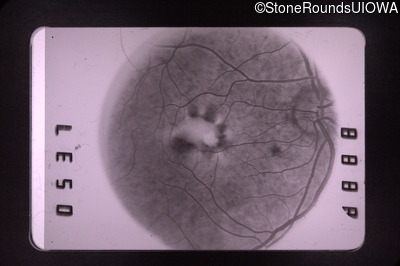

Visit at age: 59 years

Fluorescein Angiography - Right - 20/30

Exemplar